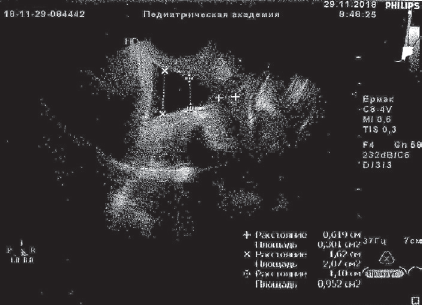

The report presents two clinical observations of pregnancy outcome in patients with isthmic-cervical insufficiency of functional (first observation) and functional-organic (second observation) origin. In both cases, previously treated cervical erosion by laser (in the second observation – carried out excision of the cervix). In secundiparous women in the present pregnancy were noted recurrent urogenital (first observation) and genital (second observation) infection with a threatened miscarriage and the need for re-hospitalizations. Complex therapy with the introduction of obstetric discharge pessarium was not effective enough, there were manifestations of the inflammatory response of the body, isthmic-cervical insufficiency progressed, up to prolapse of the fetal bladder into the cervical canal (first observation). When entering the perinatal center, the treatment of pregnant women included methods of low-volume membrane plasmapheresis and photomodification of blood with ultraviolet and laser rays (alternated). In both cases, it was possible to stop the manifestations of inflammatory response, to improve the condition of the cervical canal, to prolong pregnancy to the term of normal childbirth. In the first observation, the birth occurred naturally, in the second case cesarean section was performed due to organic changes in the cervix. Childbirth, the postpartum period in women proceeded normally. Children were born healthy, full-term, develop normally, receive breastfeeding.